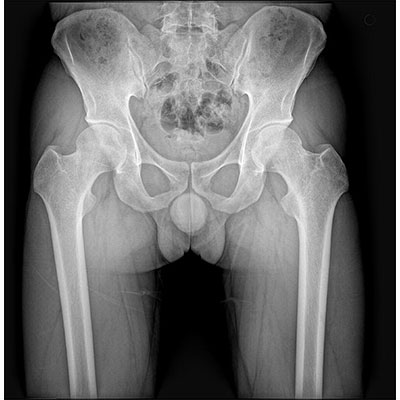

● 采用自主研發(fā)的技術(shù),在保證優(yōu)質(zhì)圖像的前提下,大大降低X射線(xiàn)劑量,用心呵護醫護工作者及患者的健康。

● 短曝光時(shí)間,便于老年人、兒童、殘疾人進(jìn)行臨床拍攝。避免這類(lèi)群體因不能有效控制身體運動(dòng)等因素造成的運動(dòng)偽影,提高攝片質(zhì)量及效率。